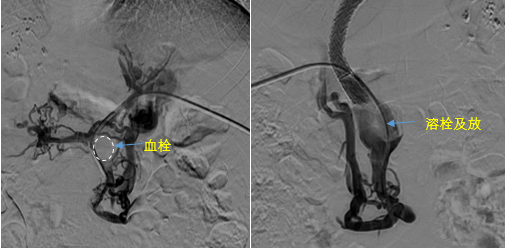

在西安國(guó)際醫(yī)學(xué)中心醫(yī)院,韓國(guó)宏教授對(duì)李女士進(jìn)行了細(xì)致的問(wèn)診及檢查,在CT圖像上仔細(xì)的分析,針對(duì)患者特殊的病情制定了詳細(xì)的治療方案。第一次進(jìn)入手術(shù)室,在DSA的監(jiān)測(cè)下,造影過(guò)程中門(mén)靜脈血栓的輪廓逐漸顯現(xiàn)出來(lái),見(jiàn)多識(shí)廣的醫(yī)生們也大吃一驚,發(fā)現(xiàn)遠(yuǎn)端脾靜脈及腸系膜上靜脈也存在大量血栓?;颊叩氖彻芪傅嘴o脈曲張非常嚴(yán)重,疏通堵塞的門(mén)靜脈已是刻不容緩。

見(jiàn)此情形,韓國(guó)宏教授憑借豐富的臨床經(jīng)驗(yàn)很快調(diào)整了策略,在超聲診療中心的協(xié)助下進(jìn)行門(mén)靜脈右支穿刺,并進(jìn)行造影,看到目標(biāo)血管后,韓國(guó)宏教授用“明修棧道,暗渡陳倉(cāng)”的方法,讓來(lái)自脾臟和胃腸的血流終于暢通的回流到了肝靜脈。通過(guò)血流的沖刷以及抗凝溶栓藥物的作用,幾日后復(fù)查造影發(fā)現(xiàn)門(mén)靜脈血栓已逐漸變小,不會(huì)對(duì)回流到肝臟的血流產(chǎn)生大的阻礙作用,門(mén)靜脈的壓力顯著減小,患者再次出血的幾率也隨之降低。幾經(jīng)周折,這顆“定時(shí)炸彈”終于被拆除,李女士和她的家人多年來(lái)心里的石頭也終于落地。